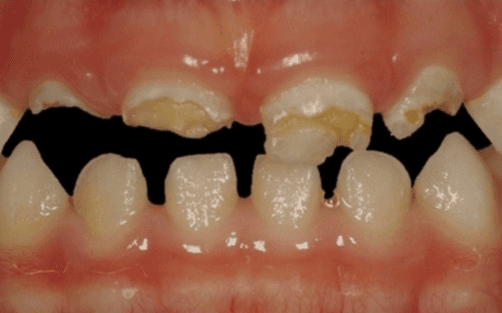

La carie nel bambino è una delle principali cause, insieme all’ortodonzia, di richiesta di intervento del dentista. La patologia ha una evoluzione particolarmente rapida in virtù della scarsità di smalto a difesa del dente da latte. Ciò comporta che, dal momento in cui il dente si ammala a quello in cui ne viene coinvolta la polpa (ovvero il nervo), il tempo sia veramente poco (vedi anche endodonzia pediatrica).

Spesso i dentini da latte cominciano a cariarsi già appena erompono nel cavo orale in quanto sono frequentemente a contatto con zuccheri semplici, come quelli veicolati dal biberon. Particolarmente aggressivi per i denti da latte risultano: tutte le tisane/infusi in commercio in bustine già pronte e pre-zuccherate; il latte zuccherato con qualsivoglia tipologia, incluso il miele; il latte e biscotti, specie nell’uso notturno; l’utilizzo quotidiano, spesso al posto dell’acqua, di succhi di frutta o bevande acide, per citare alcuni fra i più comuni errori commessi nel tentativo di dare una alimentazione completa al bambino, che spesso si traduce nella comparsa di una patologia chiamata